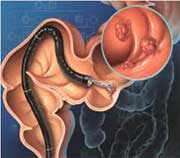

ΠΡΟΛΗΠΤΙΚΗ ΚΟΛΟΝΟΣΚΟΠΗΣΗ

Νικόλαος Αθανασόπουλος, Γαστρεντερολόγος-Ηπατολόγος-Επεμβατικός Ενδοσκόπος

Επιμελητής Γαστρεντερολογικής Κλινικής, Γενικής Κλινικής Πειραιώς «Ιπποκράτης»

Η προληπτική διενέργεια κολονοσκόπησης είναι η καλύτερη μέθοδος πρόληψης του καρκίνου του παχέος εντέρου. Ο καρκίνος του παχέος εντέρου αποτελεί το δεύτερο πιο συχνό καρκίνο του ανθρώπου (συνολικά σε άνδρες και γυναίκες μετά τον καρκίνο του πνεύμονα).

ΠΩΣ ΜΠΟΡΟΥΜΕ ΝΑ ΠΡΟΛΑΒΟΥΜΕ ΤΟΝ ΚΑΡΚΙΝΟ ΤΟΥ ΠΑΧΕΟΣ ΕΝΤΕΡΟΥ

Βασιλική Αρβανίτη, Γαστρεντερολόγος-Ηπατολόγος-Ενδοσκόπος, υπ. Διδάκτωρ Πανεπιστημίου Πατρών, Μετεκπαιδευθείσα στο Λονδίνο

Επιμελήτρια Γαστρεντερολογικής Κλινικής, Γενικής Κλινικής Πειραιώς «Ιπποκράτης»

Ο καρκίνος του παχέος εντέρου είναι πολύ συχνός και αποτελεί τη δεύτερη αιτία θανάτου από καρκίνο στους άντρες μετά τον καρκίνο του πνεύμονα, και την τρίτη αιτία στις γυναίκες μετά τον καρκίνο του μαστού και του πνεύμονα.

ΠΟΛΥΠΟΔΕΣ ΠΑΧΕΟΣ ΕΝΤΕΡΟΥ

Μυρωνίδης Λεωνίδας, Γαστρεντερολόγος, Επεμβατικός Ενδοσκόπος

Το εσωτερικό τοίχωμα του εντέρου που ονομάζεται βλεννογόνος αποτελεί μία λεία επιφάνεια που παρουσιάζει αναδιπλώσεις και πτυχές. Όταν σε ένα σημείο ο βλεννογόνος χάσει αυτή την ομαλή εμφάνιση και αποκτήσει ένα οζίδιο που προβάλλει εντός του αυλού του εντέρου, μοιάζει σαν ένα μικρό κουνουπίδι, σαν μανιτάρι, σαν την σταφυλή που έχουμε στο λαιμό μας, τότε ονομάζουμε τη βλάβη αυτή πολύποδα του εντέρου.